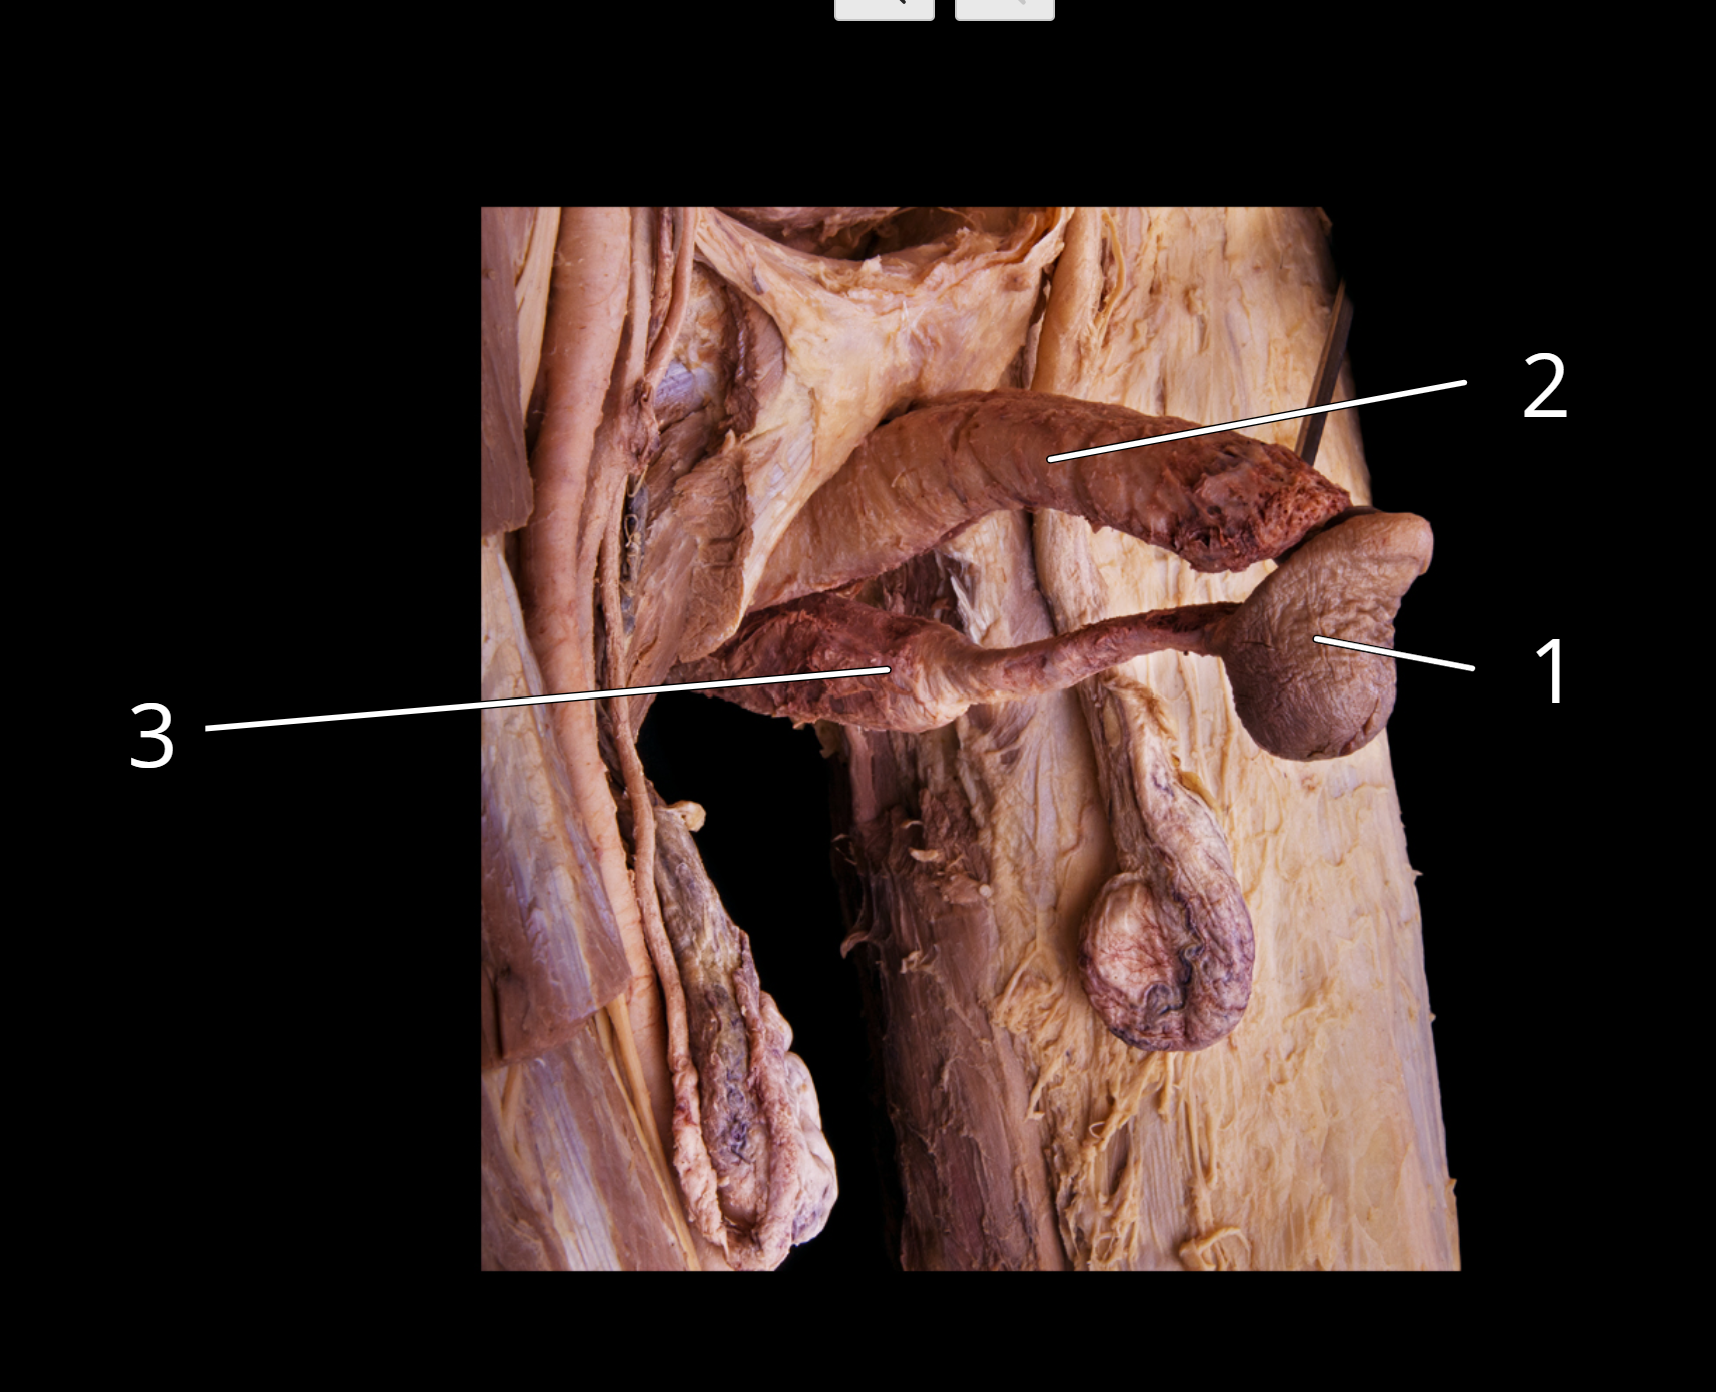

Structures of the penis

1. Glans penis

2. Corpora cavernosa

3. Corpus spongiosum